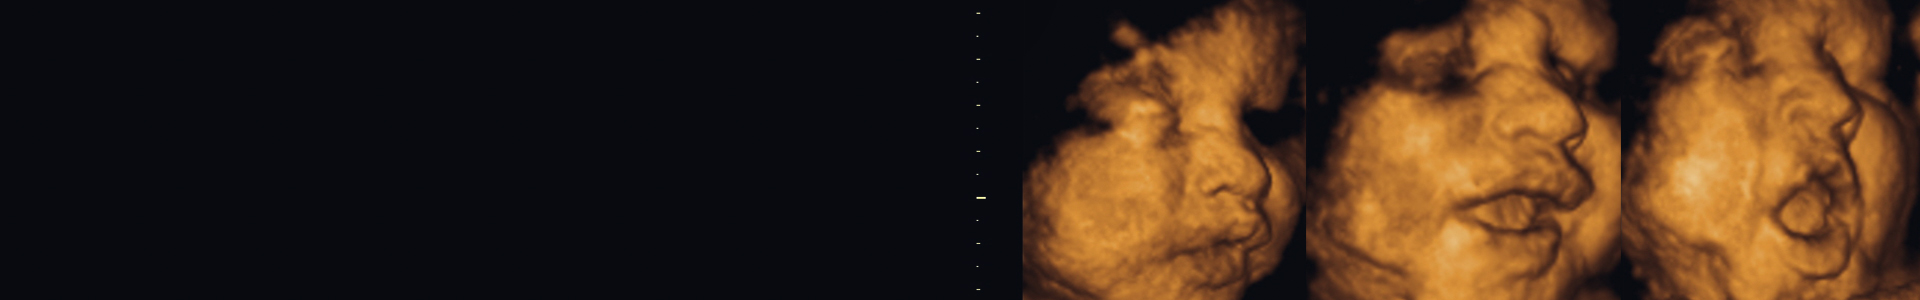

With this ultrasound the baby’s face, laughs and yawns are visible 3D/4D/5D. Sometimes we can see how the baby is attached to the umbilical cord, and other gestures in real time that brings tenderness to your family.

This is one of the most popular tests chosen by patients and family members. This because the ultrasound images are very attractive and reflect the external anathomy of the baby. The images can be with movement or without, the first one is commonly called fourth dimension. We perform it between the 10 and 39 weeks of pregnancy.